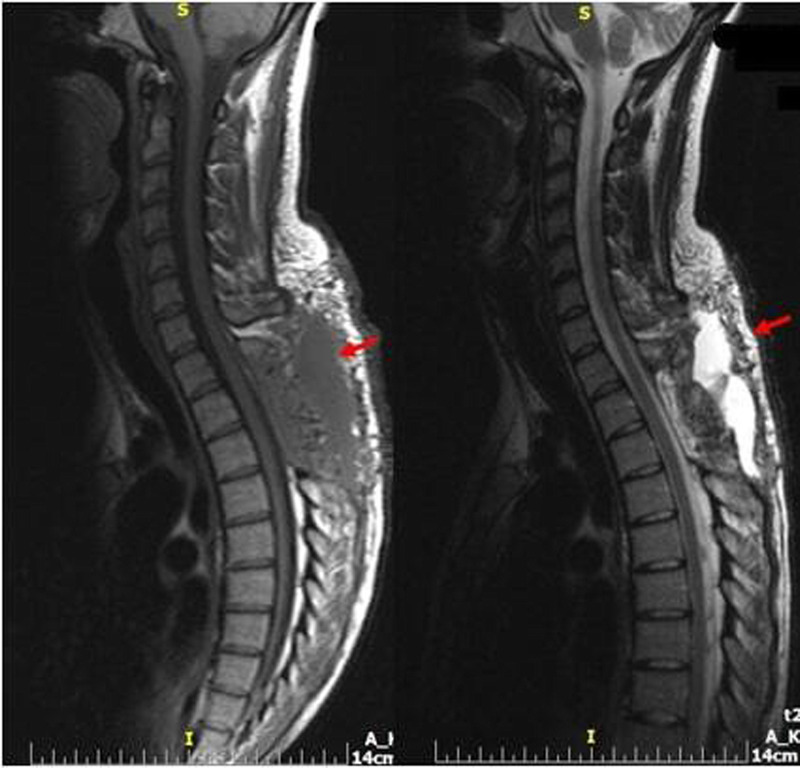

自发性脊髓硬膜外血肿(SSEH)是罕见的,特别是在怀孕期间。然而,SSEH是一种严重的紧急情况,必须立即处理,以防止母亲的永久性神经缺陷和死产。SEEH的病因和发病机制尚不清楚,尽管文献中描述了多种理论和诱发因素。在这个报告中,我们描述了一个怀孕的女性谁发展SSEH的情况。患者提供书面和知情同意发表她的临床信息和相关图像。在这里,我们报告了一例24岁的女性,孕龄31周,已知因子S缺乏和狼疮抗凝剂阳性,正在接受低分子肝素(LMWH)治疗。这种治疗有可能导致出血。此外,患者报告有10天的背部、乳房和下肢麻木和疼痛史。无外伤史报道。患者表现为急性(12小时)截瘫,立即在当地医院进行了磁共振成像(MRI)扫描,发现T1-T3位背侧硬膜外间隙急性出血(图1,2)。给予皮质类固醇,并通过直升机将患者转移到我们的急诊科,神经学评估显示双下肢力量受损(右:3/5,左:1/5),以及轻触丧失。心脏摄影和腹部超声显示心动过缓,脉搏中位数约为每分钟98次